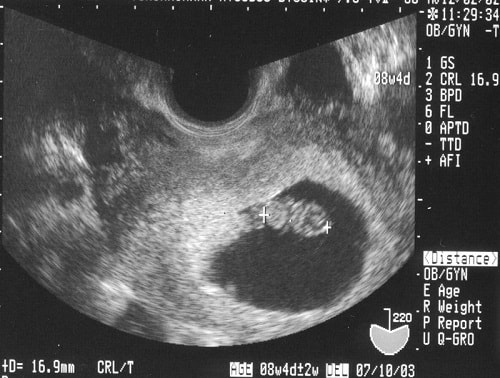

Hình ảnh siêu âm thai 4 tuần tuổi

Khi thai được 4 tuần tuổi, mẹ bầu có thể đi siêu âm để nhìn thấy con yêu. Giai đoạn này thai đang bắt đầu quá trình làm tổ. Trong quá trình siêu âm mẹ bầu sẽ thấy được vị trí của thai, túi thai…

Thời điểm 4 tuần thai còn quá nhỏ, nên các chỉ số siêu âm lần này chưa thể chính xác hoàn toàn. Nên mẹ bầu hãy đợi lần siêu âm kế tiếp để quan sát con yêu kỹ hơn nhé.